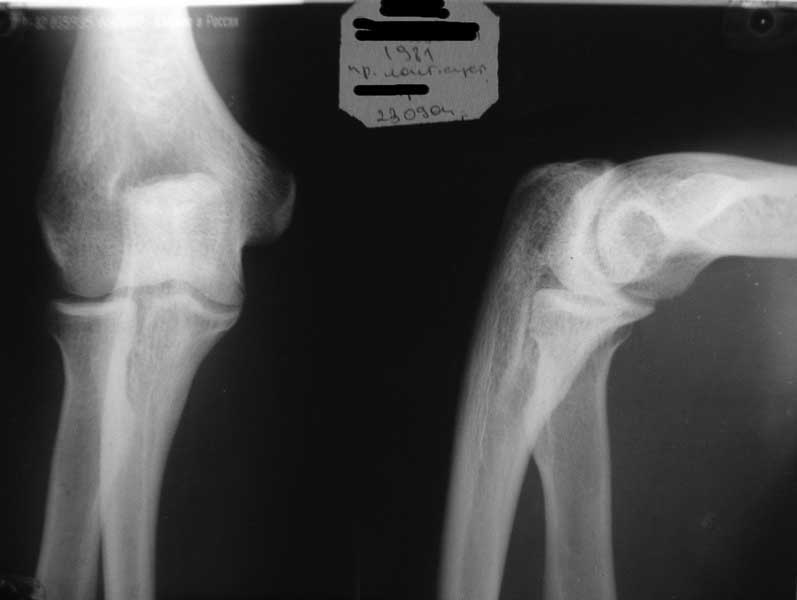

Уважаемые коллеги! Требуется ваша помощь. На консультацию обратился пациент 30 лет с

Пассивные в полном объеме. Со слов имела место некая родовая травма. К тому же отмечается незначительный

имеется контрактура локтевого сустава: сгибание в полном объеме, разгибание 150 градусов,

супинация в пределах 7 градусов. Функция конечности в принципе устраивает. Скелетных травм

в анамнезе нет. Вопрос: есть ли смысл заниматься какими-либо реконструкциям на плечевом

суставе и как можно улучшить функцию скомпрометированных суставов? Заранее всем

благодарен